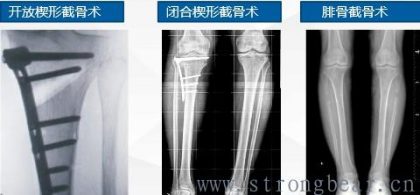

三 截骨术

四 HTO历史